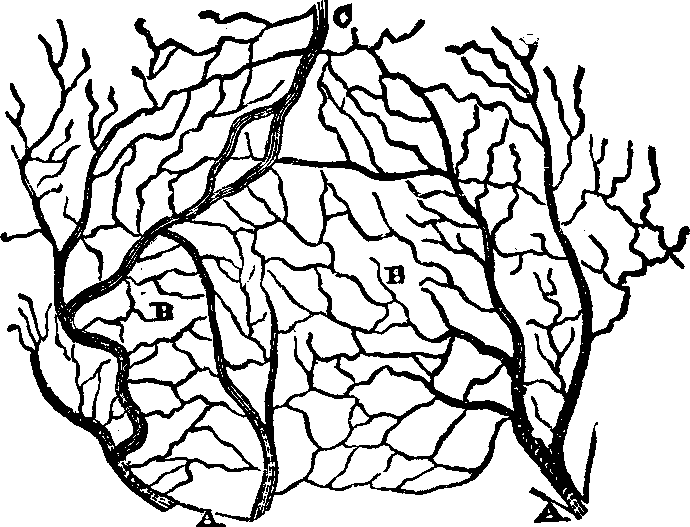

substance, and the arrangement of the pigmentary matter. C.

Transverse sections, showing the distinction between the cortical and

medullary substances, and the central collection of pigmentary matter,

sometimes found in the latter. Magnified 310 diameters.

Hairs are horny appendages of the skin, and, with the exception

of the hands, the soles of the feet, the backs of the fingers and toes,

between the last joint and the nail, and the upper eyelids, are distributed

more or less abundantly over every part of the surface of the body. Over

the greater part of the surface the hairs are very minute, and in some

places are not actually apparent above the level of the skin; but the hair

of the head, when permitted to reach its full growth, attains a length of

from twenty inches to a yard, and, in rare instances, even six feet. A hair